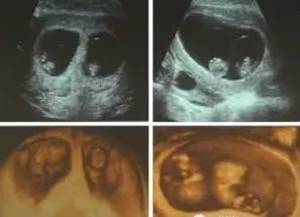

现在随着辅助生育技术的普及,多胎妊娠率增加。早期B超如果发现双胎妊娠,在医生判断母亲身体允许双胎妊娠情况下,早孕期行三维超声检查,可明确双胎的绒毛膜羊膜属性,预测双胎的产科风险;如发现是三胎以上妊娠,则应尽早行选择性胚胎减灭术,越早进行风险越小,保证母胎安全。

(图:(左)超声下双绒毛膜双羊膜囊双胎;(右)单绒毛膜双羊膜囊双胎)